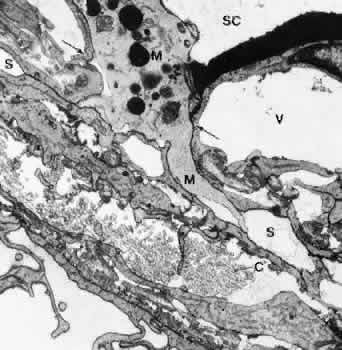

The endothelial cells of Schlemm's canal are bound together by maculae adherentes and tight junctions.8,37 However, these tight junctions do not form zonulae occludentes, but in places the adjacent cell membranes are separated, forming meandering pathways between interdigitating cell processes. These pathways are often open toward both the cribriform layer and the lumen of the canal (Fig. 16). Anterior chamber perfusion with cationized ferritin in rhesus monkeys has shown that these particles predominantly pass through the paracellular routes.8,9 Often these routes are locally expanded, so that in sagittal sections “vacuole-like” structures are formed.9 According to our observations, macrophages and leukocytes mostly pass through the paracellular routes to leave the eye rather than through the transcellular channels (Fig. 17).

Fig. 16. Structure of the inner wall endothelium (E) of Schlemm's canal (SC) showing a transcellular pathway through a giant vacuole (GV) and a paracellular route (arrow) labeled with cationized ferritin (CF). S, subendothelial cells. (Epstein DL, Rohen JW: Morphology of the trabecular meshwork and inner wall endothelium after cationized ferritin perfusion in the monkey eye. Invest Ophthalmol Vis Sci 32:160, 1991)

Fig. 17. Electron micrograph of a sagittal section through the inner wall of Schlemm's canal (SC) after anterior chamber perfusion with cationized ferritin (cynomolgus monkey, × 21,800). Note the large macrophage (M) squeezing through the intercellular space (arrows) of the inner wall endothelium of Schlemm's canal (SC). C, collagenous fibers; V, giant vacuole; S, subendothelial space.